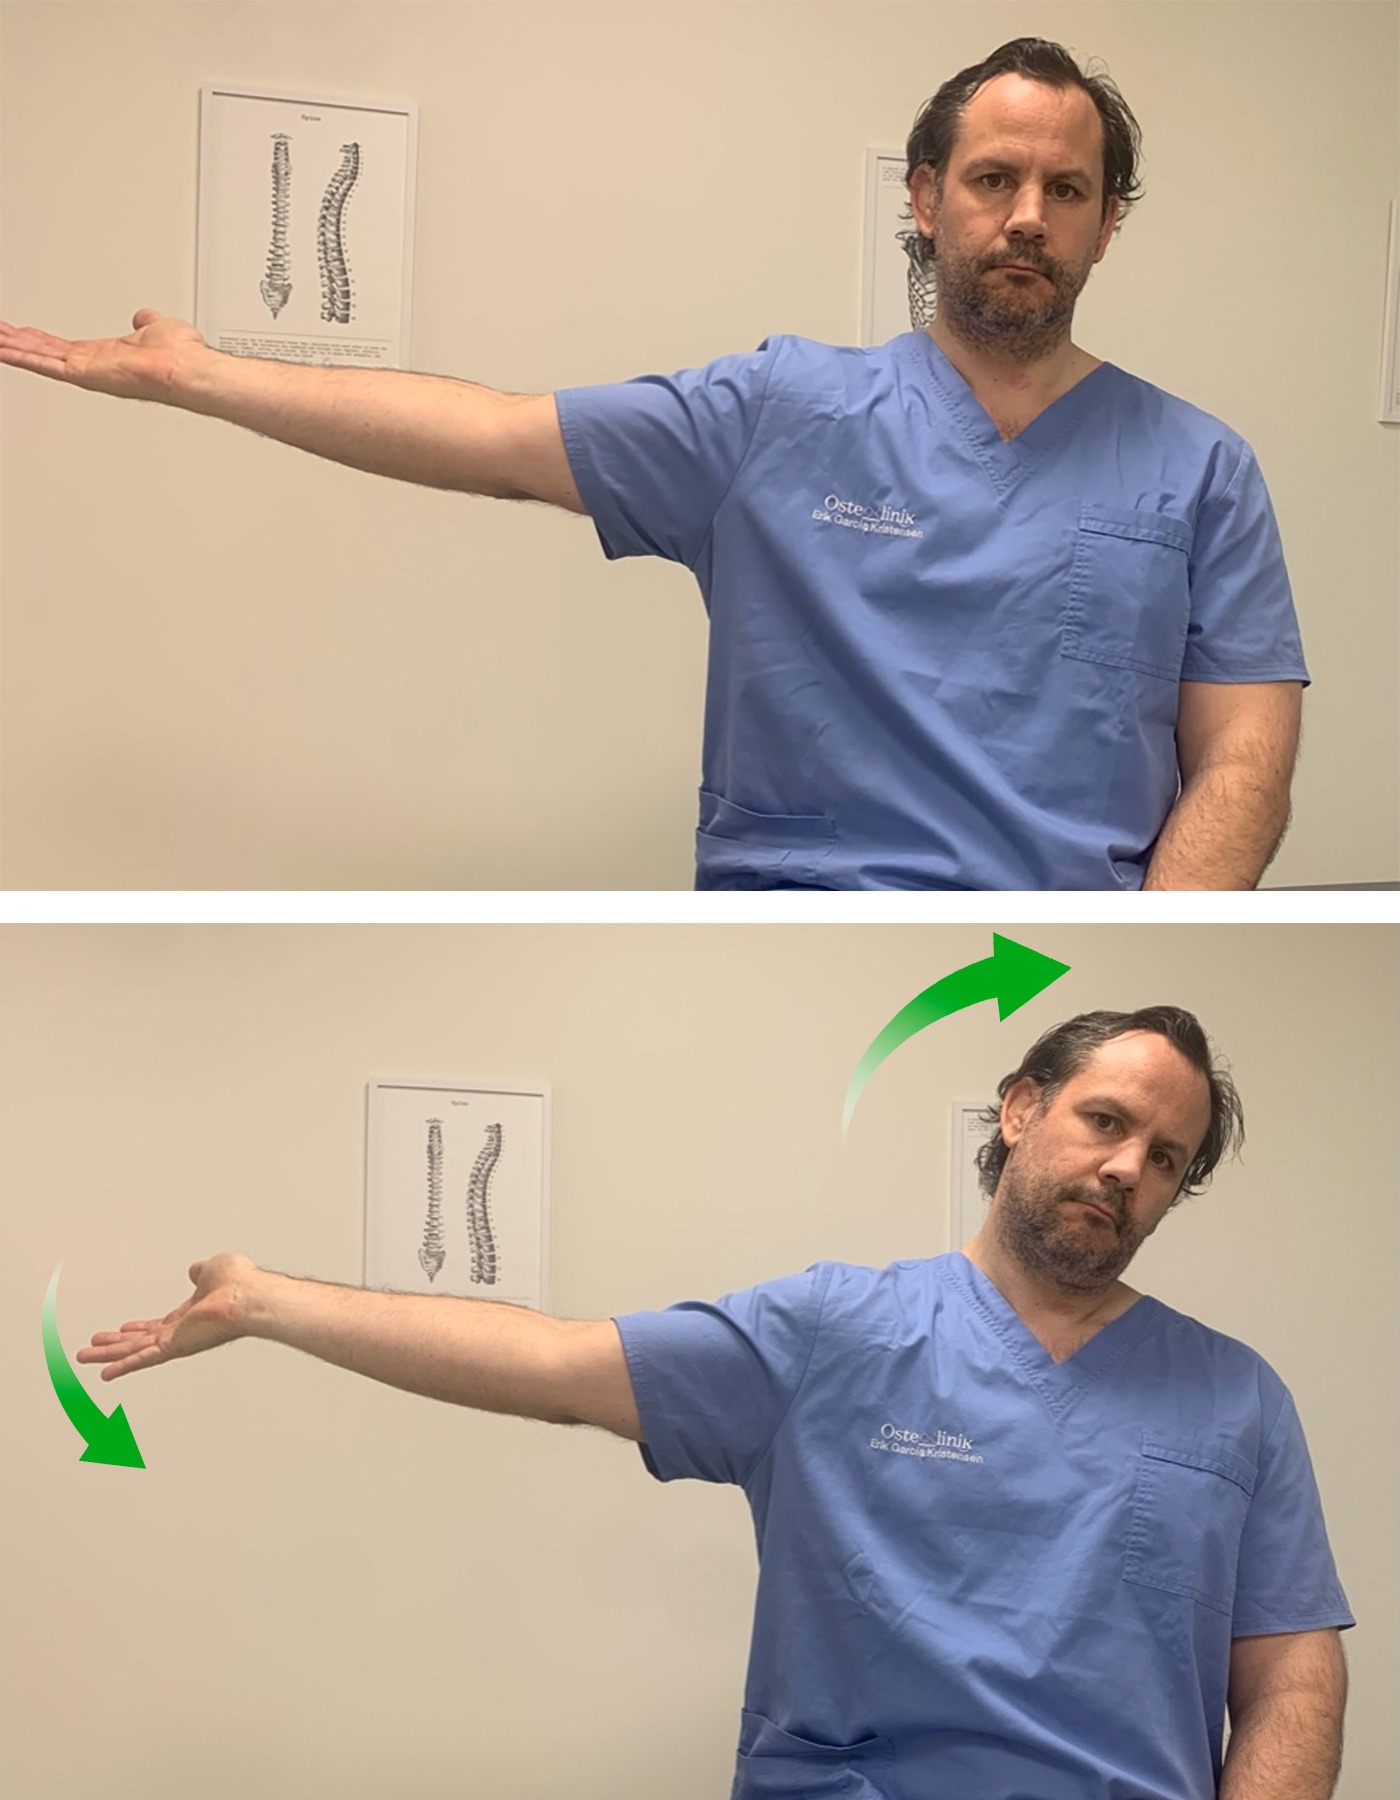

1. Nervio Mediano:

Vamos a realizar, primero, una puesta en tensión y estiramiento del nervio para después pasar a una movilización.

Partimos de una posición erguida de pie o sentado. Colocamos el brazo del lado que queremos trabajar en separación lateral de unos 90º, con la palma de la mano mirando hacia arriba. Vamos a realizar una flexión dorsal de la muñeca y mantenemos el codo extendido.

Para aumentar la tensión, inclinamos lateralmente la cabeza hacia el lado contrario.

De esta manera estamos poniendo en tensión el nervio mediano y podemos sentir la sensación de tensión y cierto hormigueo en el brazo y la mano.

Aguantamos unos segundos en esta posición y pasamos a trabajar el deslizamiento del nervio. Para ello, inclinamos la cabeza hacia el lado afecto (deberemos notar en este momento que desaparece la tensión y el hormigueo). Y ahora volvemos a inclinar la cabeza hacia el lado contrario a la vez que hacemos una flexión palmar de la muñeca. Cuando llegamos al límite de movimiento, inclinamos la cabeza de nuevo hacia el lado afecto y hacemos otra vez flexión dorsal de la muñeca.

El ejercicio consiste en alternar inclinación contraria de la cabeza + flexión palmar de la muñeca y inclinación hacia el lado de la lesión + flexión dorsal.

Realizaremos este ejercicio en 3 series de 10 repeticiones.

1. Estiramiento

2. Movilización- deslizamiento